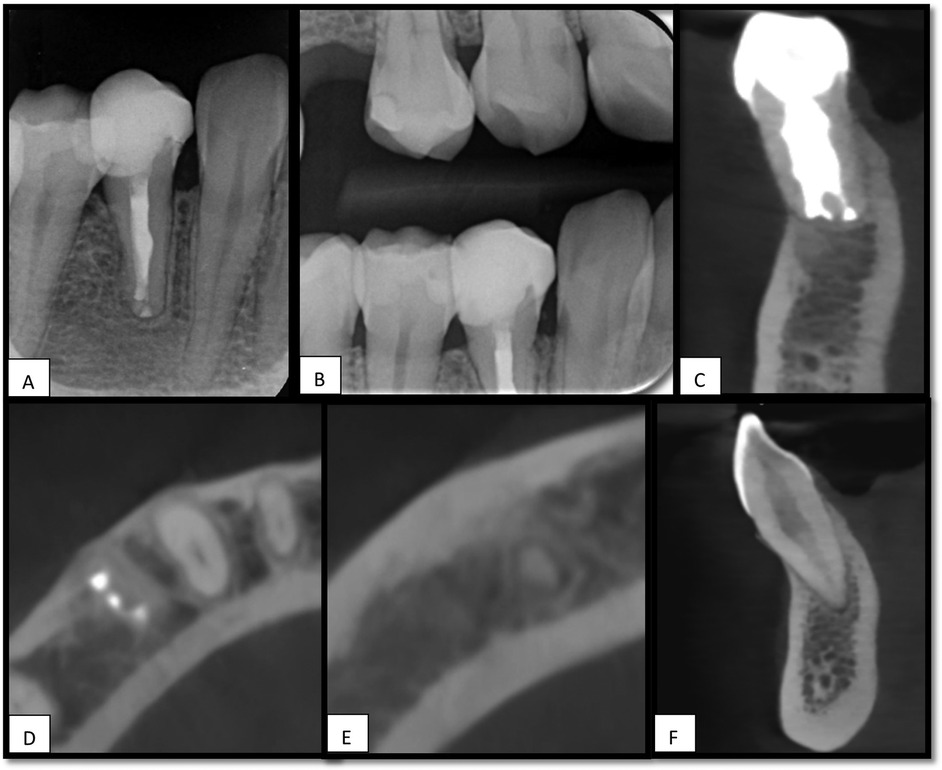

Clinical and radiographic follow-ups, including periapical radiographs and CBCT scans over 15 months, demonstrated successful periapical healing, functional stability, and the absence of progressive resorptive changes. This case highlights the effectiveness of IR as a tooth-preserving strategy for complex resorptive cases.

Follow-up evaluations demonstrated recovery of normal pulpal sensibility in tooth #43, a mild response to cold testing, and a positive response to electric pulp test, accompanied by complete periapical bone regeneration. CBCT imaging revealed signs of healing in the previously detected periapical radiolucency associated with tooth #43, which was observed before treatment for tooth #44 (Figure 4).

Figure 4. 15 months follow-up, (A), periapical x-ray for tooth #44, shows healing of apical radiolucency. (B), Bitewing x-ray. (C), Sagittal view of CBCT for tooth #44 shows no signs of root resorption. (D,E), Axial view of CBCT shows healing of periapical area associated with teeth #44 and #43. (F), Sagittal view shows no RL associated with tooth #43.

This case report presents a 15-month follow-up of IR for the management of a mandibular premolar (44) exhibiting extensive apical root resorption. The clinical and radiographic outcomes demonstrated favorable healing without evidence of ankylosis or root resorption, supported by normal tooth mobility, physiological response to percussion, and radiographic demonstration of an intact periodontal ligament space. Although many resorption-related complications tend to manifest within the first year post-replantation (14), long-term monitoring remains essential to capture late-onset complications (15).